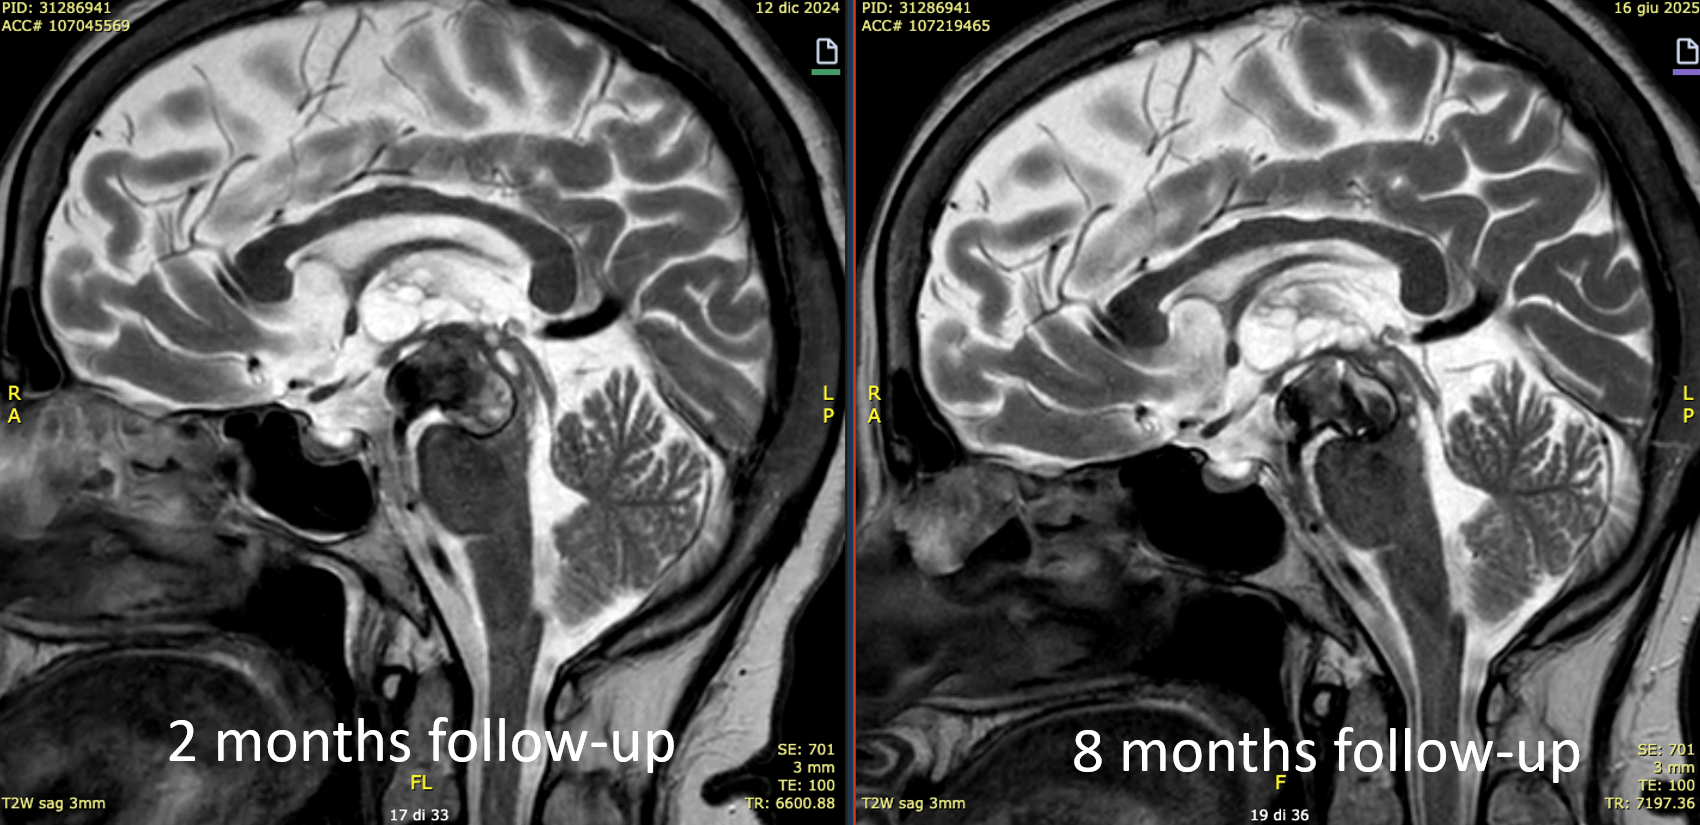

At the 8 months follow-up, after passing from DAPT to SAPT, the aneurysm became smaller, with corresponding clinical improvement.

This is a key point — the success of treatment in aneurysms of this type is judged by cross-sectional imaging, not angio. With aneurysm shrinkage a good angiogram is guaranteed, while there are many examples of good-looking angiograms with moribund patients.